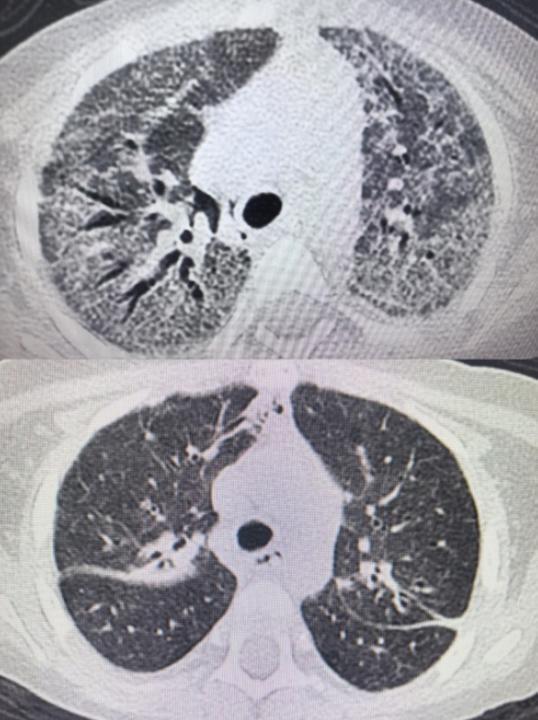

2025年12月10日,小佩因发热2天、气促半天被收治入院。该患儿一年前确诊急性淋巴细胞白血病,此次在维持化疗阶段发生肺部耶氏肺孢子菌感染,病情迅速进展为重度急性呼吸窘迫综合征并继发呼吸衰竭,后进一步发展为肺纤维化。入院时,小佩表现为呼吸急促、精神萎靡、尿量减少及经皮血氧饱和度持续下降,生命体征不稳。

针对肺部感染及纤维化,救治团队先后实施五次纤维支气管镜下肺泡灌洗术及其他最新治疗措施,并根据病情动态调整抗感染方案。

在60天救治过程中,小佩的呼吸支持方式经历了从无创通气、气管插管、气管切开,最终降至鼻导管吸氧的逐步过渡,肺功能逐步恢复。